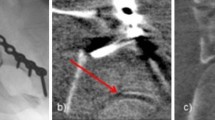

Intra-operative fluoroscopic imaging

Both intra-operative fluoroscopic 2D and 3D-imaging were performed with the BV Pulsera with 3D-RX (3 Dimensional Rotational X-ray) [9]. The BV Pulsera (Philips Healthcare, Best, the Netherlands) consists of a mobile C-arm unit modified to provide a motorized rotational movement and is combined with a Philips 3D-RA workstation. For a single 3D scan, a series of 225 2D fluoroscopic images is acquired over a period of 30 s during a 200° rotation of the C-arm (Fig. 1). The projection images are used to reconstruct a 3D data set. Both volume-rendering and slice images in the axial, coronal and sagittal planes were available. The slice images were considered to provide the best information and were used solely in clinical practice (Fig. 2). From autumn 2005, 3D-imaging of the BV Pulsera was used in a research setting; from 2007, the BV Pulsera was clinically available. From 2009, the images could be enhanced by coloring the metal implants present (Titanview software, Philips Healthcare, Best, the Netherlands).

3D-images of intra-articular step, gap and implant position of the calcaneus; Sagital (a), axial (b) and coronal slice images (c, d) of intra-operative fluoroscopic 3D-imaging. Titanview software is used to color the metal implants present (Titanview software, Philips Healthcare, Best, the Netherlands). a Step-off in calcanocuboid (CC) joint. b Gap in calcanocuboid (CC) joint. c Step-off in posterior talocalcaneal (PTC) joint. d Intra-articular position of a screw in the posterior talocalcaneal (PTC) joint

The radiation exposure of each image in the scanning run is dynamically adjusted to provide the best combination of low dose and optimal image quality. The maximum equivalent dosage of a 3D scan of the calcaneus with the BV Pulsera is 17 mSv. Because 3D-imaging is more time-consuming and requires additional preparation to remain sterility, 3D-imaging was used additional to 2D-imaging at the surgeon’s preference.